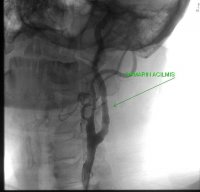

56 yaşında diyabet hastalığı ve sigara içme alışkanlıkları olmayan erkek hasta baş ağrısı ve baş dönmesi şikayetleri ile kliniğimize başvurdu. Karotis arter tıkanıklığı teşhisi konulan hastaya karotis stentleme işlemi yapıldıktan sonra iyilik hali ile taburcu edildi.